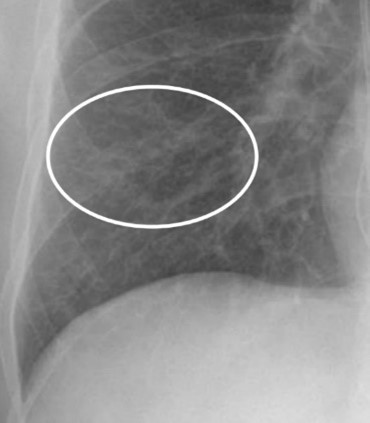

Små nodulära förändringar, kring pleuran, men också runt kärl liksom mellan lober, mellan bronker – Vilka diagnoser överväger du nu? Vad blir nästa steg?

Sarkoidos, även amyloidos som differentialdiagnos, liksom tuberkulos.

DT lunga

Vad visar bilden?

Små nodulära förändringar, kring pleuran, men också runt kärl liksom mellan lober, mellan bronker typiskt vid sarkoidos, även amyloidos som differentialdiagnos, liksom tuberkulos.